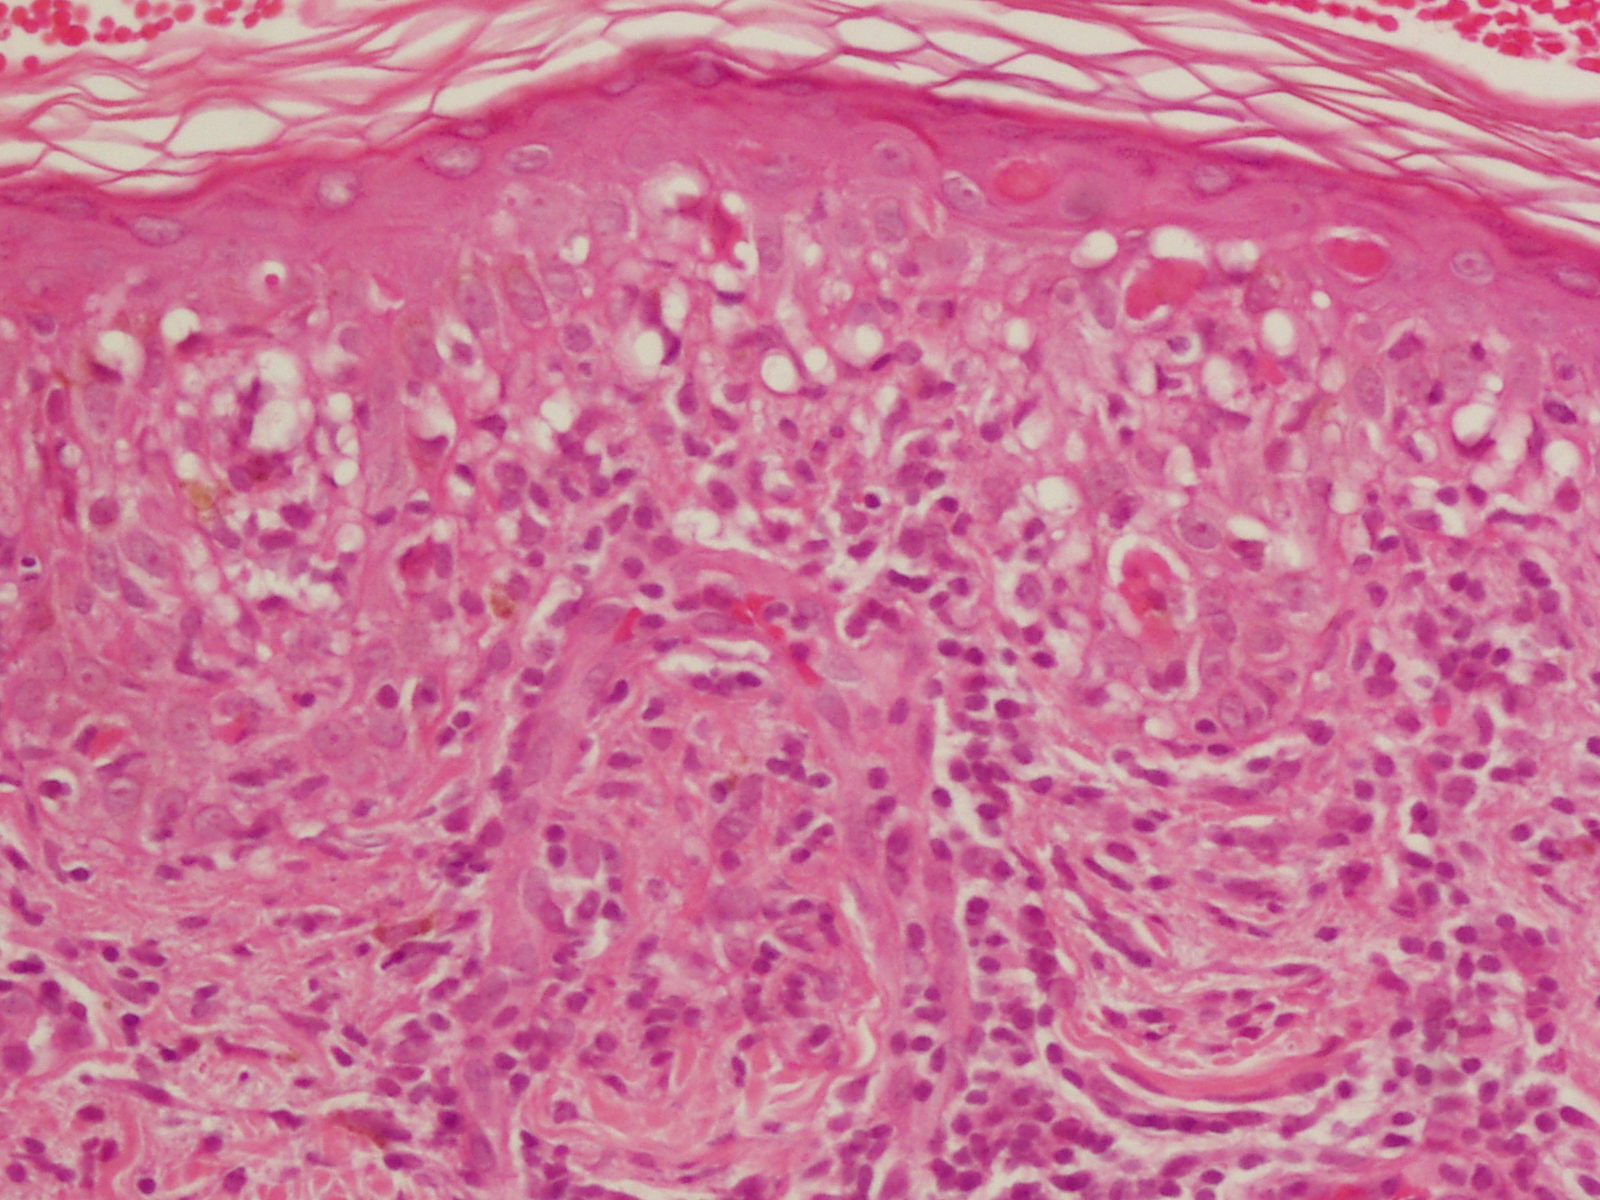

dermpat -- p1013516.jpg